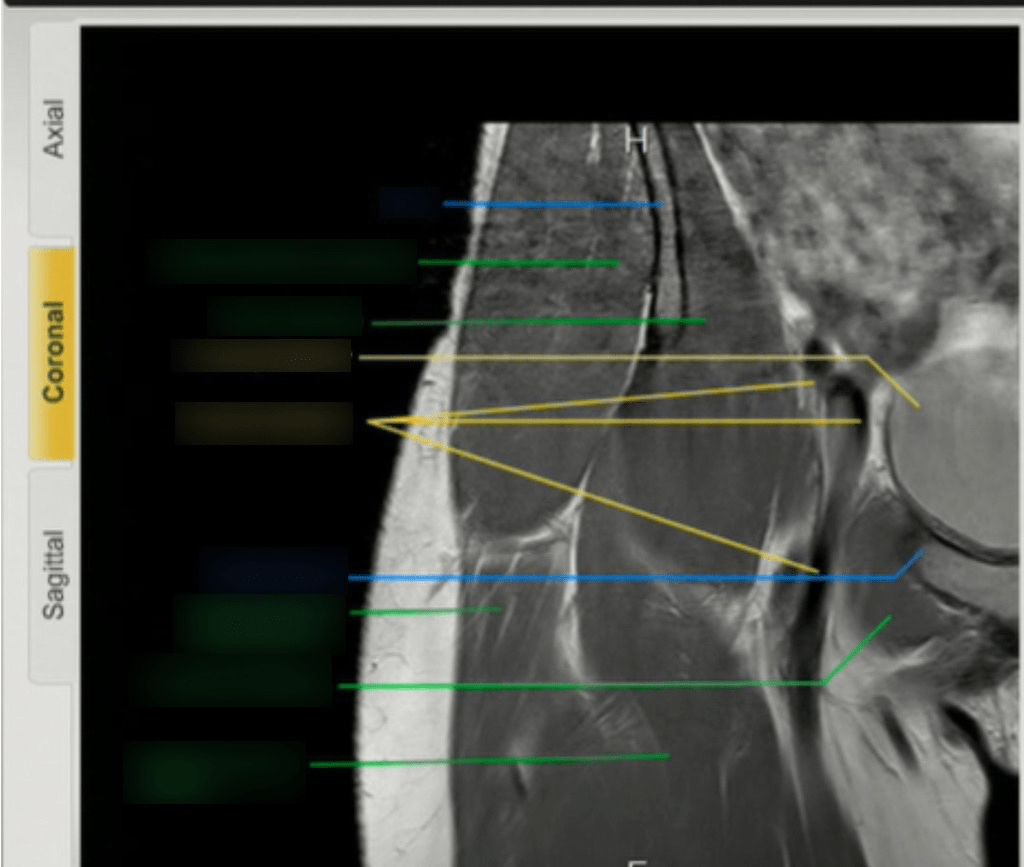

Chronic Shoulder Pain Coronal Mri Hip Your guide to hip health imaging. This mri hip joint coronal cross sectional anatomy tool is absolutely free to use. Mri coronal cross sectional anatomy of hip. Mri arthrogram with joint distension can differentiate between perilabral cyst and perilabral sulcus anterosuperior cleft partial extension of fluid into the anterosuperior labrum on. Unenhanced mri, indirect mr arthrography, and direct mr arthrography. Coronal Mri Hip.